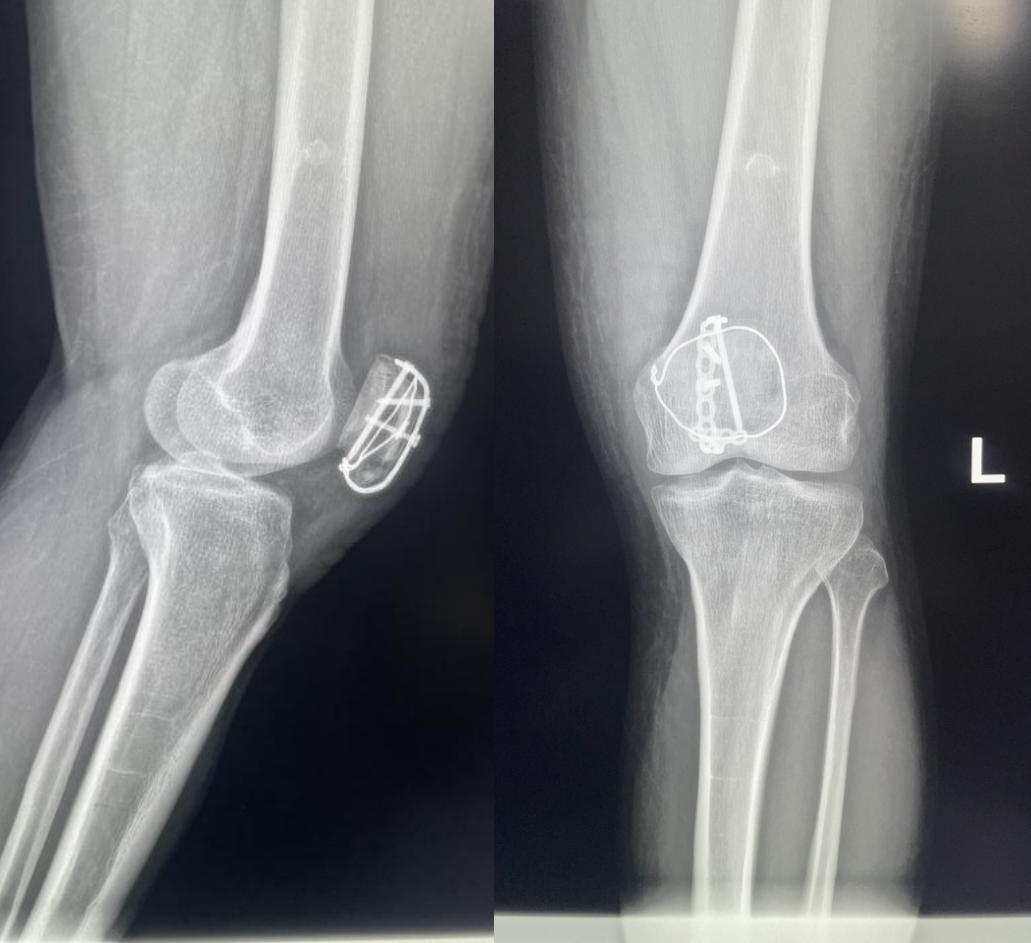

髌骨骨折只占全身骨折的 1%,治疗方式的选择和并发症的防治尤其要注意,急诊来了髌骨骨折患者,你怎么处理?髌骨是人体最大的籽骨,位于膝关节伸膝装置内。解剖特点包括近端宽大的基底和关节外的远侧尖端,前面位于关节外,后面为关节面。股直肌和股中间肌止于髌骨基底部,股内侧肌和股外侧肌止于髌骨的两侧。髌腱起于髌骨尖端,止于胫骨结节。髌骨骨折约占所有骨折的 1%,主要由直接暴力造成,如跌倒时跪地或膝关节屈曲时受到打击。典型的体征包括关节肿胀、压痛、伸膝功能部分或完全丧失。除以主诉和典型体征外,膝关节 X 线片也是必不可少的一项辅助检查,以膝关节正侧位 X 线片最常见,如果怀疑纵向骨折,膝关节屈曲 45° 时髌骨 30° 切位片可以辅助诊断。对于骨折不愈合、畸形愈合所致的关节面不平整以及髌股关节对应关系不良可采用 CT 检查。MRI 有助于诊断软骨缺损和损伤。34-B 型(部分关节内骨折,伸膝装置完整,如纵行骨折)髌骨下极骨折袢钢板结合克氏针、张力带固定 图源:作者提供

拉力螺钉加张力带钢丝固定或经胫骨结节绕髌环扎;经骨缝合撕裂的肌腱加髌骨和胫骨结节间钢丝环绕以加固缝合;袢钢板固定。无移位采用非手术治疗;移位并且单纯骨折采用横向拉力螺钉固定,骨质疏松患者需加环扎固定;对于多骨折块(星状)则采用髌骨环扎加张力带进行固定。克氏针加张力带钢丝;有第三个骨折块则采用拉力螺钉或克氏针加张力带钢丝固定;对于 4 个或 4 个以上的骨折块采用克氏针加螺钉加张力带钢丝进行固定;对于严重粉碎和软骨面广泛破坏的髌骨骨折,髌骨部分或完全切除也是一种可行的办法。

术中切开显露髌骨时,最理想的的分离层面为皮下筋膜和伸膝装置之间,如若在皮肤和皮下筋膜之间进行分离,可能会造成伤口边缘坏死。对于开放性髌骨骨折应及时给予清创处理,对于闭合性髌骨术后感染患者应及时进行清创灌洗直至伤口愈合。如有深部感染则推荐长期使用抗生素。透明降解物会产生轻重不等的无菌性滑膜炎,这很难和感染相区分。需行关节镜检查来确定。在进行克氏针固定髌骨时,克氏针的末端应剪短,否则有穿破皮肤以及术后活动时疼痛的风险。髌骨骨折术后内植物至少在损伤后 9 ~ 12 个月才能取出。高密度的骨皮质需要这么长时间才能愈合,从而能在无保护情况下承受高张力。必须防止这一并发症的发生,因为会导致膝关节屈曲严重受限。用环扎钢丝来保护髌腱时,有可能因为错误估计髌腱长度而造成髌骨低位。髌骨的正常位置可以参照健侧膝关节的 X 线片。屈曲受限的患者需要进行强化理疗。如果在数月内运动的范围没有增加,下一步可行关节镜下松解,去除髌上囊的挛缩瘢痕。如果髌骨已切除,则可能出现肌腱断裂的晚期并发症。髌骨软骨面的严重损伤、关节面不平整的继发性损伤以及髌股关节受力的改变,都将导致创伤性关节炎的发生。如果髌骨韧带附着位置太靠前方,会使髌骨下极位置靠后,也将导致创伤性关节炎。在前一种情况下,可以行关节镜下清理;后一种情况下需改变韧带附着点位置。髌骨术后应及时有效地进行膝关节活动锻炼,一般在术后 3 月时膝关节可屈曲 120° 以上,若术后 3 月时膝关节弯曲角度仍然小于 90°,建议进行辅助康复训练,必要时以手术松解。